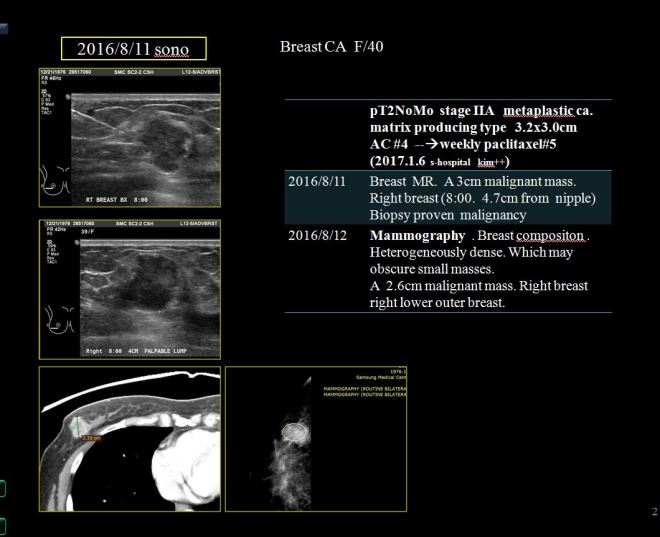

• 2016.8.11 – 유방암 대략 3cm 우측 유방에 발견

• S 병원에서 수술. 유방암 stage는 2기A로 판명

• 2016.9월부터 2017.1월까지 AC #4 시행함

• 2017.1부터 주마다 paclitaxel 시행함. zoladex도 사용함

• 2017.2.22 7차 항암 이후 손발저림이 심해서 리리카를 복용하고 어지러움증과 불면 지속

• 2017.3.29 paclitaxel #12 차 종료

• CT상 폐전이 발견. 방사선치료 예정 있었으나 폐전이 발견돼 중지

• 2017.3.31 CT chest – 다발적 폐전이와 종격동 림프절전이 발견

cancer 2017-07-005 전영옥 유방암.jpg이 환자는 40세의 젊은 아이들의 엄마로 유방암을 발견하고서 S 의원에서 수술을 받았다. 이 환자는 유방에 흔히 있는 invasive ductal carcinoma와는 다른 pathology를 진단받았다. 이 pathology는 metaplastic carcinoma로 약간의 sarcomatoid component를 지닌 독특한 종양이다. 자료에 의하면 유방암 환자 중에 0.25 – 1% 사이에서 이 같은 진단을 받는 환자가 나타난다. 또한 이들의 양상은 호르몬수용체나, 림프절전이는 적으면서 high grade의 큰 종양으로 발견되는 경향이 있으며, 5년생존율이 일반적은 invasive ductal cacrcinoma보다 못한 49% – 68% 정도이다. 즉 반 정도가 5년 내에 사망한다고 볼 수 있다 (아래 원문참조).

초기에 수술 전에 약 3.2×3.0cm 정도의 크기를 보였고 우측 유방절제 후에 소음인에게 잘 맞는 AC 요법을 4 차 2016년 9월부터 2017년 1월까지 시행하였다.